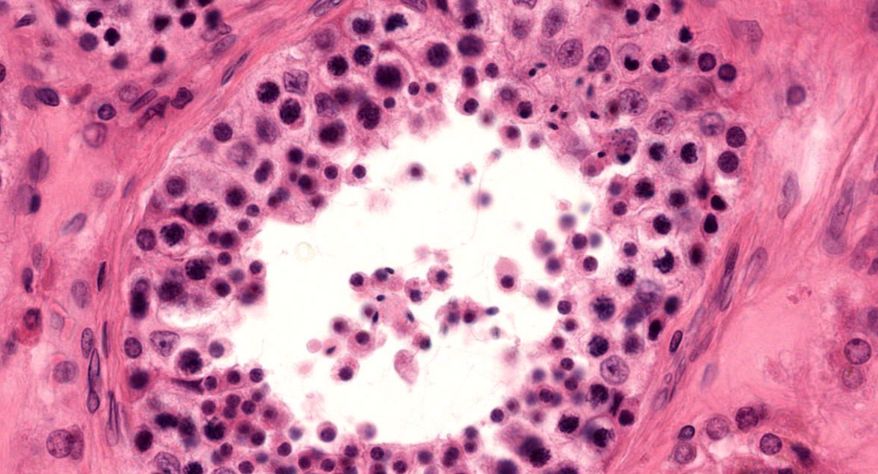

低倍镜:睾丸表面为鞘膜覆盖,其上皮为单层扁平上皮,鞘膜下是一层较厚的致密结缔组织,叫做白膜。白膜在睾丸后缘增厚,形成睾丸纵隔,其内可见不规则的腔隙,即睾丸网。睾丸内可见很多上皮性管道的切面,即生精小管的切面,呈圆形或椭圆形,管壁较厚,由生精上皮及其明显的基膜等组成。高倍镜:着重观察生精小管和其之间的睾丸间质。生精小管主要由生精上皮构成。生精上皮由生精细胞和支持细胞组成。生精细胞是一组细胞,依次自基膜向管腔面排列。

12.睾丸间质细胞

13.直精小管

14.睾丸网